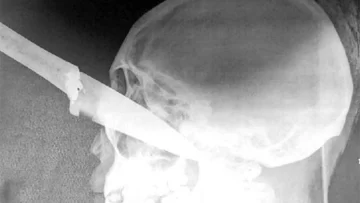

Un doctor le brindó los primeros auxilios y la llevó al hospital local, desde el cual fue trasladada en urgencia al hospital San Bernardo con el diagnóstico de "herida punzo cortante por arma blanca en el interior del globo ocular". Los cirujanos tuvieron que realizarle una evisceración ocular y su estado sigue siendo delicado.